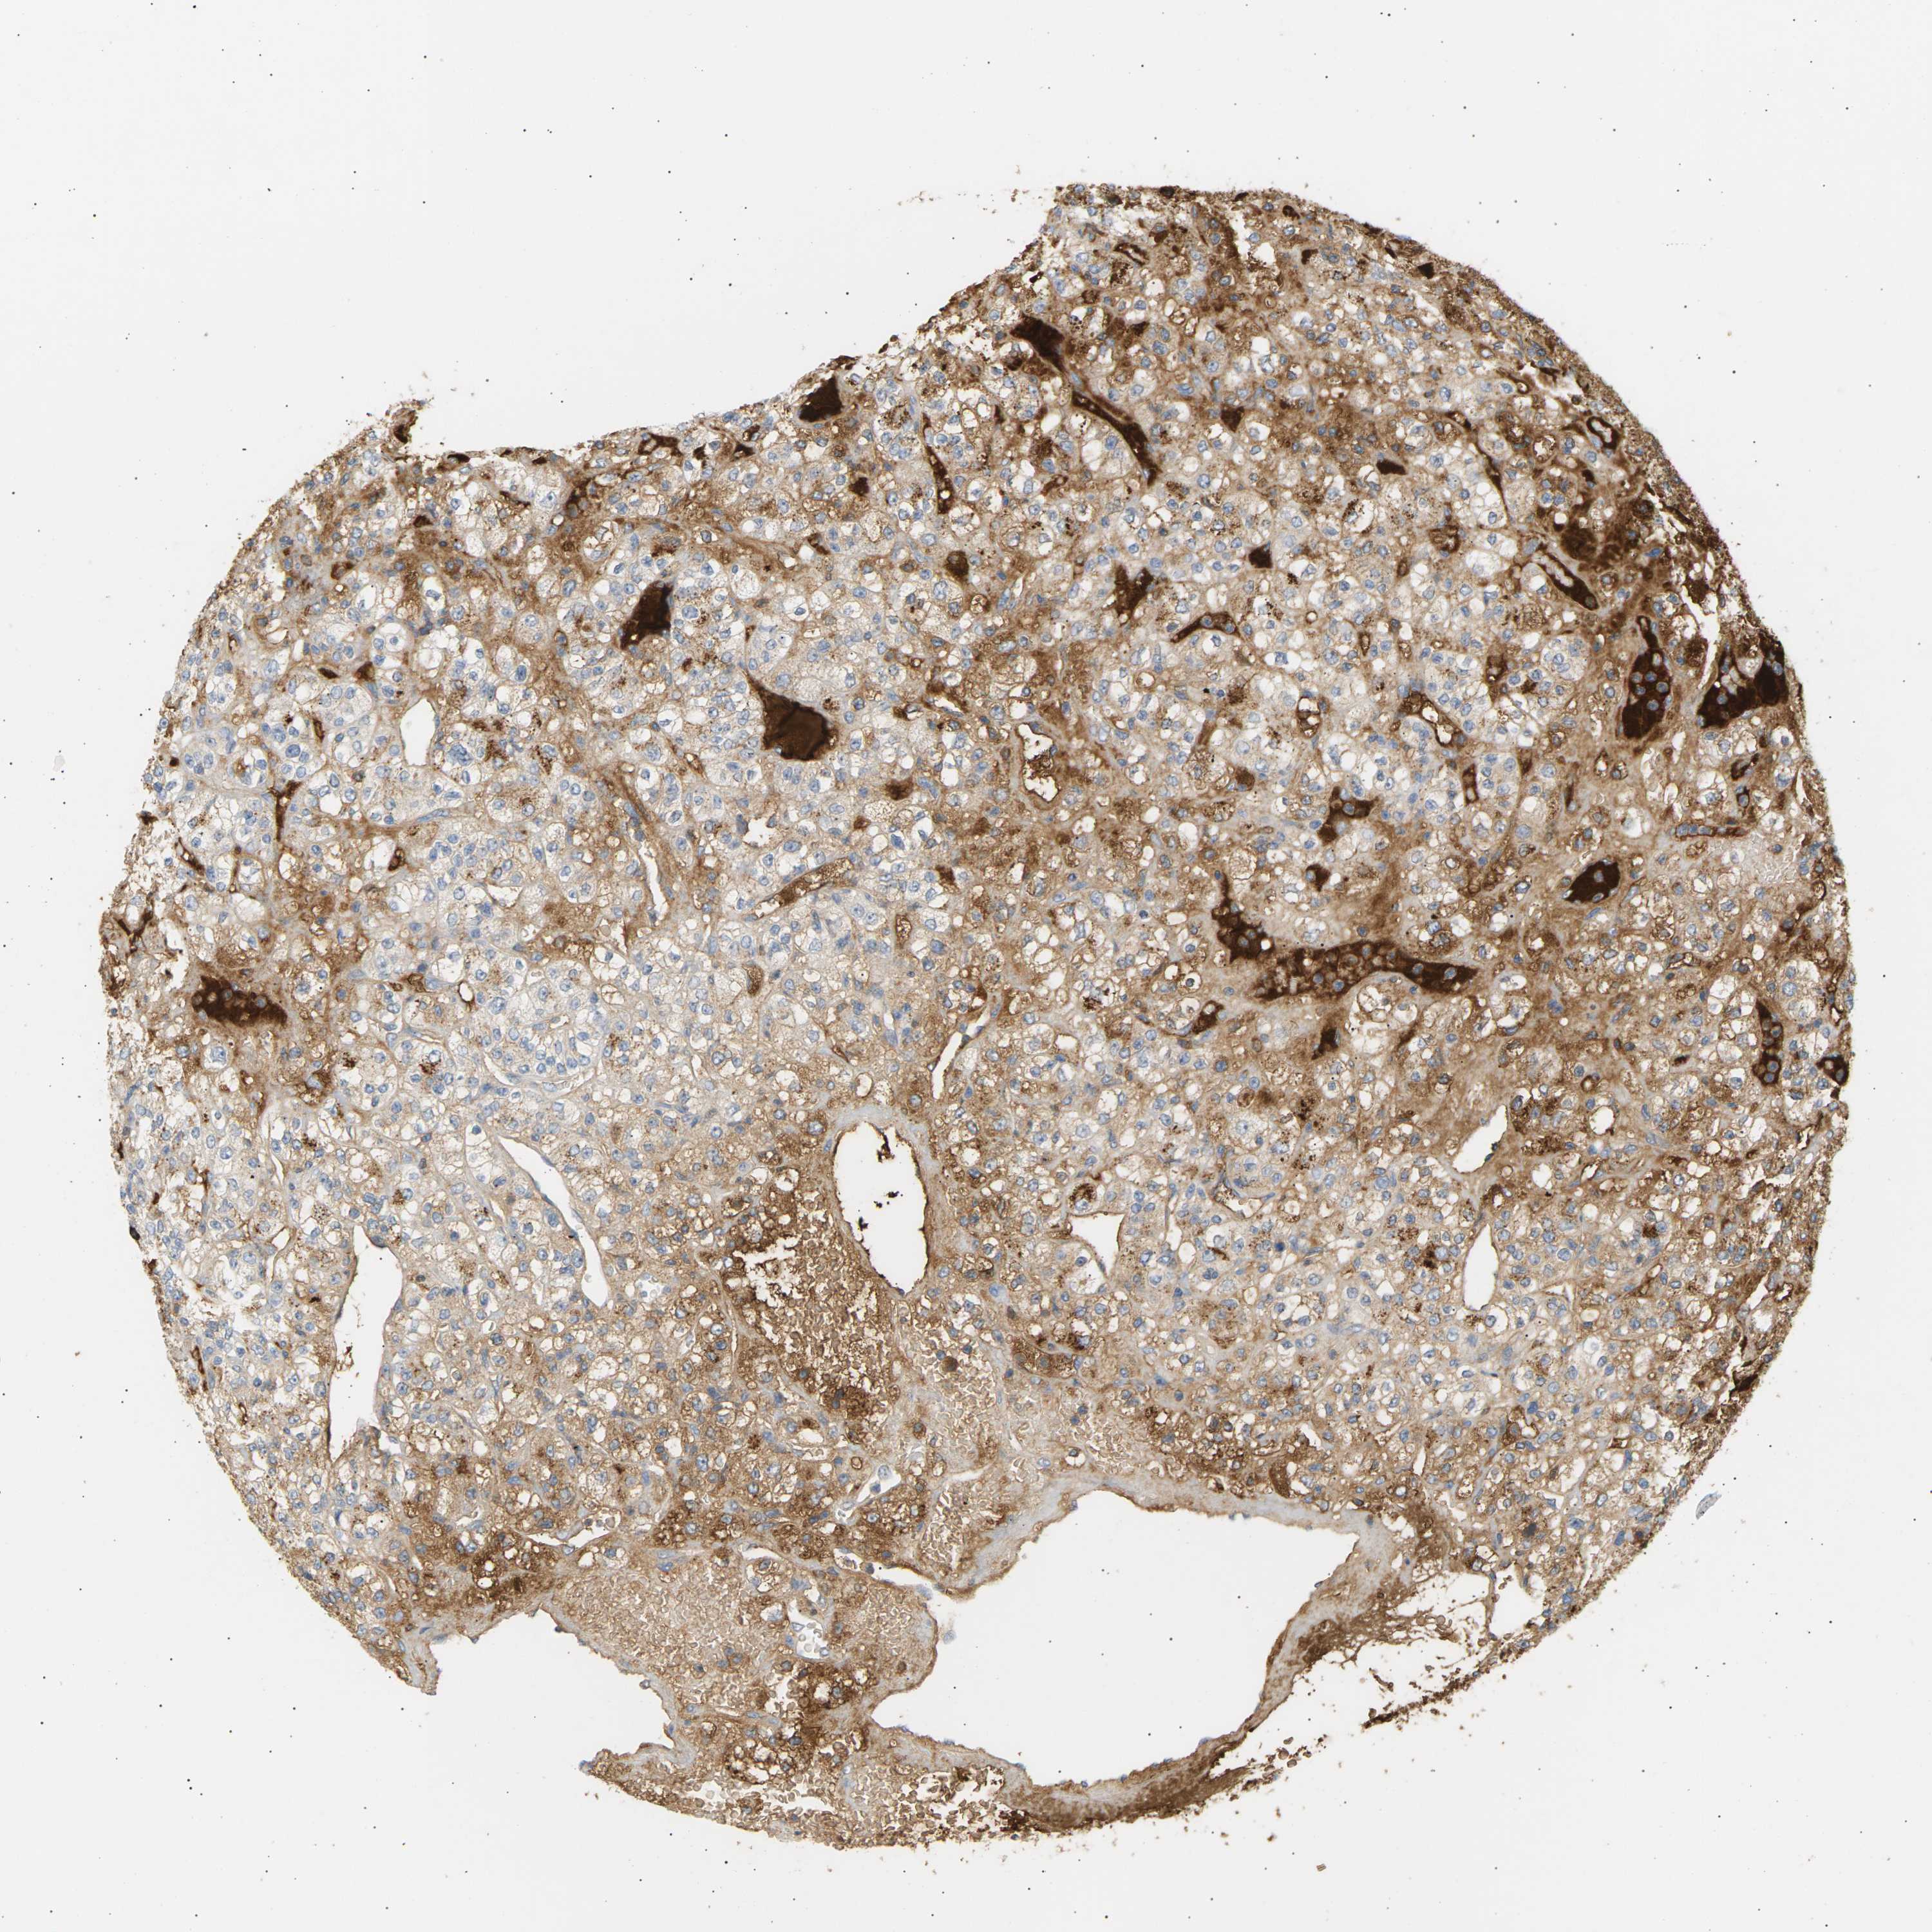

IGLC3 is potential prognostic, high expression is unfavorable in Kidney Renal Clear Cell Carcinoma (TCGA)

Best expression cut offi

Based on the FPKM value of each gene, patients were classified into two groups and association between prognosis (survival) and gene expression (FPKM) was examined. The best expression cut-off refers the FPKM value that yields maximal difference with regard to survival between the two groups at the lowest log-rank P-value. Best expression cut-off was selected based on survival analysis .

When clicking on this number, the vertical dashed line indicating cut-off, the interactive survival plot, and the Kaplan-Meier curve will be adjusted to show results based on the best expression cut-off.

: 719.21

TCGA RNA samplesi

RNA-seq data is reported as average FPKM (number Fragments Per Kilobase of exon per Million reads), generated by the The Cancer Genome Atlas (TCGA) .

Normal distribution across the dataset is visualized with box plots, shown as median and 25th and 75th percentiles. Points are displayed as outliers if they are above or below 1.5 times the interquartile range. FPKM values of the individual samples are presented next to the box plot.

Average pTPM 1190.2

Number of samples 521